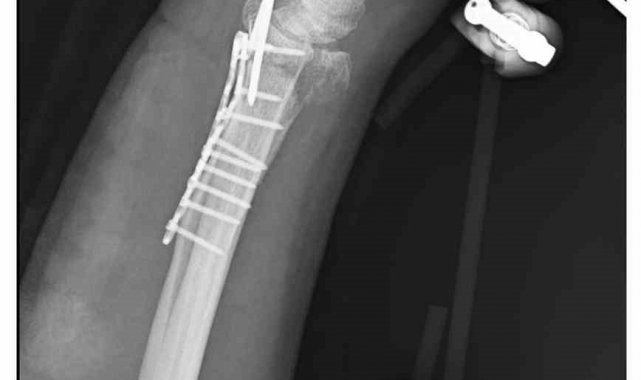

"Bileğimde 15 dikiş ve 11 platin var"

Yasin Arslantaş, "Sabah apartmandan çıkış yaptığım sırada arkamdan 9 köpeğin geldiğini gördüm. Saldırgan haldelerdi. Bana saldırmak üzerelerdi. Kaçmaya çalışırken ayağım kaydı ve düştüm. Bileğimde 15 dikiş ve 11 platin var. İki ay boyunca kolum bu halde kalacak ve ardından da yine 2 buçuk ay fizik tedavi süreci olacak. Doktorlar his ve hareket kaybımın olacağını söylediler. Bileğimden büyük kemiğin kırılmasından dolayı zorlu bir süreç geçiriyorum. 3 saatlik bir ameliyat geçirdim" dedi.